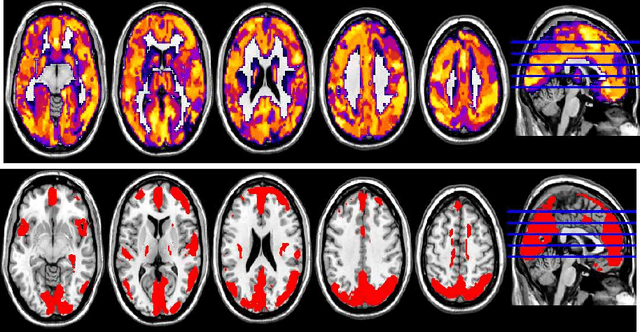

Abstract:Feature selection is among the most important components because it not only helps enhance the classification accuracy, but also or even more important provides potential biomarker discovery. However, traditional multivariate methods is likely to obtain unstable and unreliable results in case of an extremely high dimensional feature space and very limited training samples, where the features are often correlated or redundant. In order to improve the stability, generalization and interpretations of the discovered potential biomarker and enhance the robustness of the resultant classifier, the redundant but informative features need to be also selected. Therefore we introduced a novel feature selection method which combines a recent implementation of the stability selection approach and the elastic net approach. The advantage in terms of better control of false discoveries and missed discoveries of our approach, and the resulted better interpretability of the obtained potential biomarker is verified in both synthetic and real fMRI experiments. In addition, we are among the first to demonstrate the robustness of feature selection benefiting from the incorporation of stability selection and also among the first to demonstrate the possible unrobustness of the classical univariate two-sample t-test method. Specifically, we show the robustness of our feature selection results in existence of noisy (wrong) training labels, as well as the robustness of the resulted classifier based on our feature selection results in the existence of data variation, demonstrated by a multi-center attention-deficit/hyperactivity disorder (ADHD) fMRI data.

Abstract:In this paper, we focus on how to locate the relevant or discriminative brain regions related with external stimulus or certain mental decease, which is also called support identification, based on the neuroimaging data. The main difficulty lies in the extremely high dimensional voxel space and relatively few training samples, easily resulting in an unstable brain region discovery (or called feature selection in context of pattern recognition). When the training samples are from different centers and have betweencenter variations, it will be even harder to obtain a reliable and consistent result. Corresponding, we revisit our recently proposed algorithm based on stability selection and structural sparsity. It is applied to the multi-center MRI data analysis for the first time. A consistent and stable result is achieved across different centers despite the between-center data variation while many other state-of-the-art methods such as two sample t-test fail. Moreover, we have empirically showed that the performance of this algorithm is robust and insensitive to several of its key parameters. In addition, the support identification results on both functional MRI and structural MRI are interpretable and can be the potential biomarkers.

Abstract:In this paper, we consider voxel selection for functional Magnetic Resonance Imaging (fMRI) brain data with the aim of finding a more complete set of probably correlated discriminative voxels, thus improving interpretation of the discovered potential biomarkers. The main difficulty in doing this is an extremely high dimensional voxel space and few training samples, resulting in unreliable feature selection. In order to deal with the difficulty, stability selection has received a great deal of attention lately, especially due to its finite sample control of false discoveries and transparent principle for choosing a proper amount of regularization. However, it fails to make explicit use of the correlation property or structural information of these discriminative features and leads to large false negative rates. In other words, many relevant but probably correlated discriminative voxels are missed. Thus, we propose a new variant on stability selection "randomized structural sparsity", which incorporates the idea of structural sparsity. Numerical experiments demonstrate that our method can be superior in controlling for false negatives while also keeping the control of false positives inherited from stability selection.